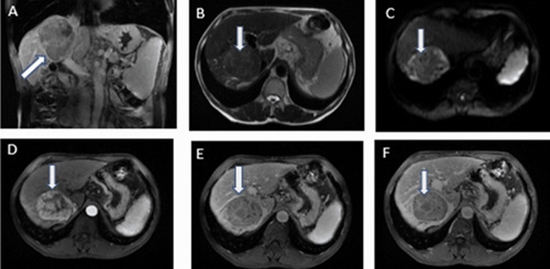

Comparing Texture Analysis of Apparent Diffusion Coefficient MRI in Hepatocellular Adenoma and Hepatocellular Carcinoma

Aim: This study aimed to assess the effectiveness of using MRI-apparent diffusion coefficient (ADC) map-driven radiomics to differentiate between hepatocellular adenoma (HCA) and hepatocellular carcinoma (HCC) features.

Materials and methods: The study involved 55 patients with liver tumors (20 with HCA and 35 with HCC), featuring 106 lesions equally distributed between hepatic carcinoma and hepatic adenoma who underwent texture analysis on ADC map MR images. The analysis identified several imaging features that significantly differed between the HCA and HCC groups. Four classification models were compared for distinguishing HCA from HCC including linear support vector machine (linear-SVM), radial basis function SVM (RBF-SVM), random forest (RF), and k-nearest neighbor (KNN).

Results: The k-nearest neighbor (KNN) classifier displayed the top accuracy (0.89) and specificity (0.90). Linear-SVM and KNN classifiers showcased the leading sensitivity (0.88) for both, with the KNN classifier achieving the highest precision (0.9). In comparison, the conventional interpretation had lower sensitivity (70.1%) and specificity (77.9%).

Conclusion: The study found that utilizing ADC maps for texture analysis in MR images is a viable method to differentiate HCA from HCC, yielding promising results in identified texture features.